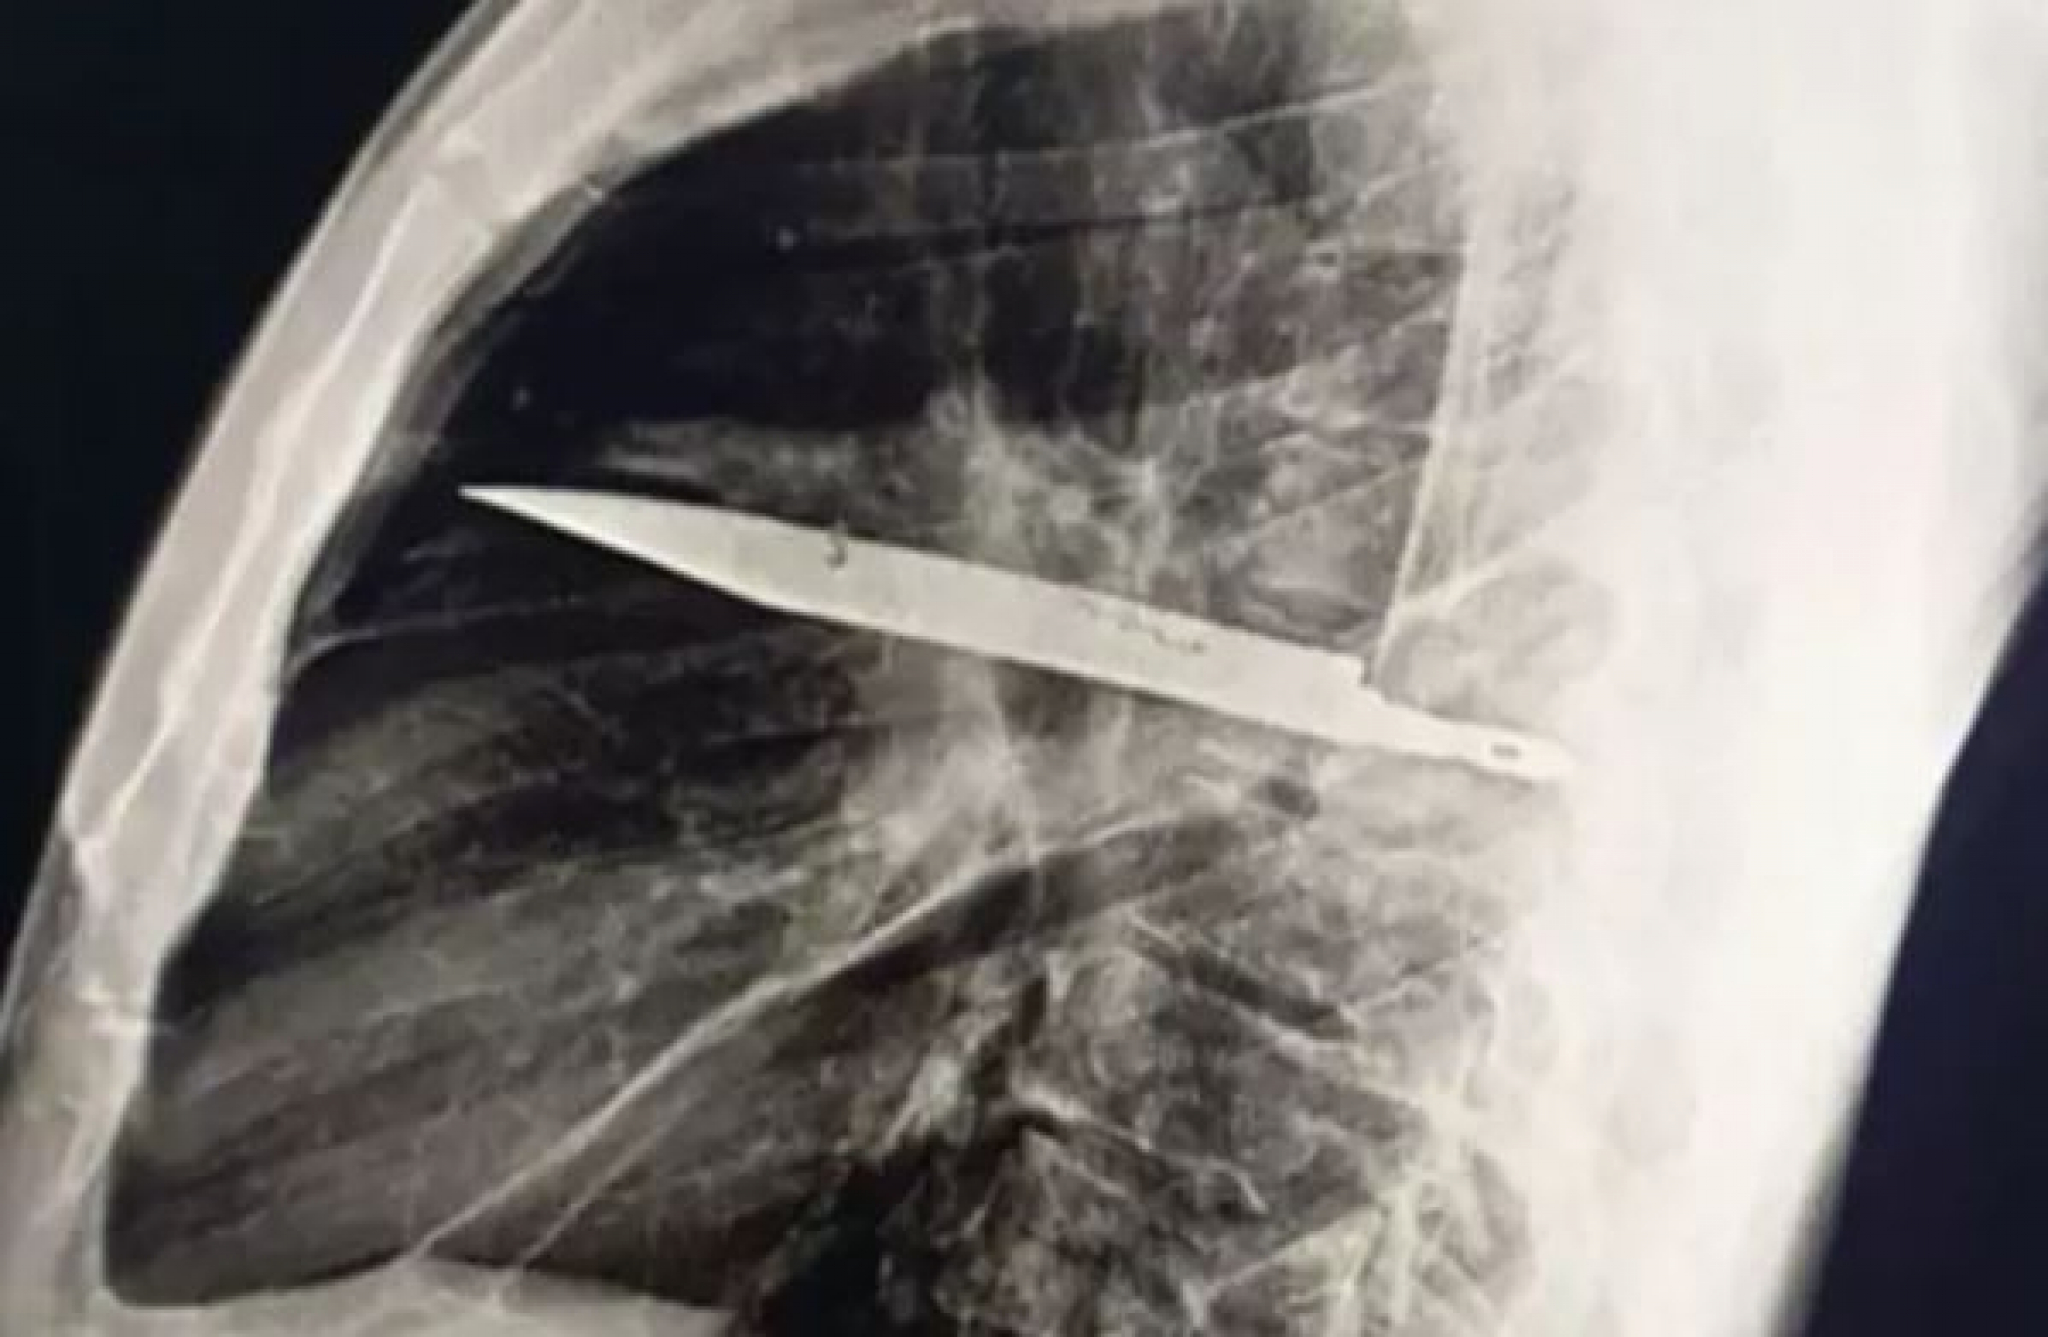

U početku je izgledalo zabrinjavajuće, ali opet – mnogi bi pomislili da je u pitanju samo neka sitna infekcija koja se lako leči antibioticima. Međutim, ispostavilo se da je razlog mnogo, mnogo gori. Rendgenski snimak pokazao je da je muškarac imao veliki nož duboko zaboden u grudima!

Godinama je živeo bez ikakvih problema, sve do trenutka kada je koža na grudima počela da otiče i kada je iz bradavice krenuo gnoj neprijatnog mirisa. Rendgen je tada otkrio "metalni predmet" – nož okružen gnojem i mrtvim tkivom.